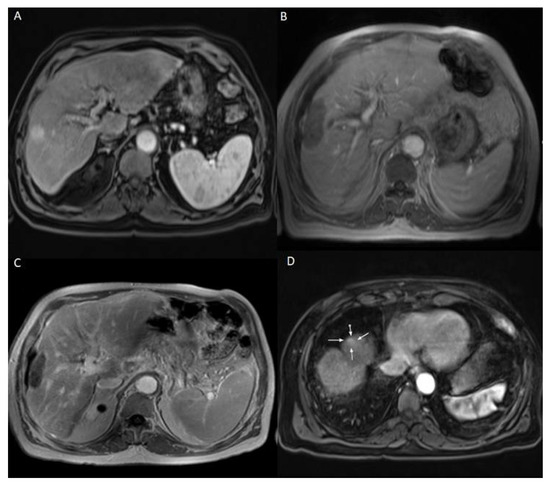

The patients who developed LTP or IDR were treated by MWA, LITT, or TACE, depending on the number, size, and location of the new HCC lesions. The decision was taken by the multidisciplinary tumor board. Examples of Patients’ cases are shown in Figure 1 and Figure 2.

Figure 1. 60 years old male patient with chronic hepatitis B virus, mild liver cirrhosis, and HCC lesion in the left liver lobe, who was treated with MWA. (A) Pre-treatment CEMRI showed a hyperenhancement of the lesion in the arterial phase. (B) During MWA. (C) 24h post-ablation CEMRI showed the completely ablated lesion. (D) 2-years post-ablation CEMRI showed a complete remission after MWA. The survival time of this patient was 21 months starting from the date of ablation until last contact.